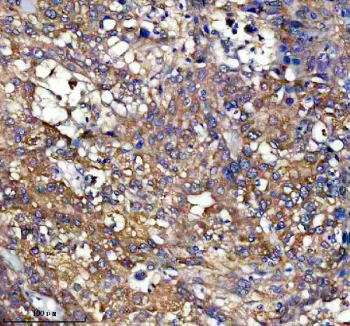

Immunohistochemical staining of PEX11B using anti-PEX11B antibody. PEX11B was detected in a paraffin-embedded section of human liver cancer tissue. Heat mediated antigen retrieval was performed in EDTA buffer (pH 8.0, epitope retrieval solution). The tissue section was blocked with 10% goat serum. The tissue section was then incubated with 1:50 rabbit anti-PEX11B antibody overnight at 4oC. Peroxidase Conjugated Goat Anti-rabbit IgG was used as secondary antibody and incubated for 30 minutes at 37oC. The tissue section was developed using an HRP secondary and DAB substrate.